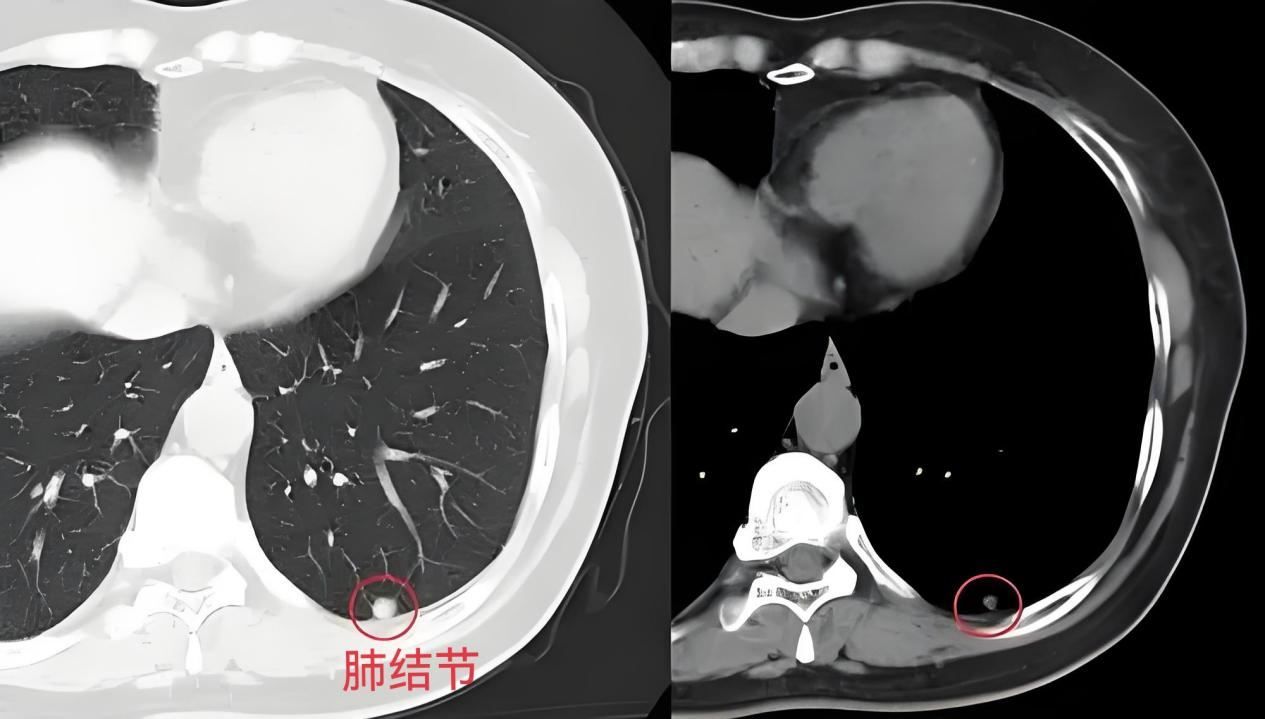

当我们拿到肺部CT报告单时,会不会因为报告单上的肺结节而感到恐慌?我们该如何分辨肺部CT报告单上的危险信号?下面带你走进影像课堂读懂肺结节,消除你的焦虑。

- 肺结节是指在影像学上表现为直径小于3厘米的类圆形或不规则形、边界清晰或不清晰的密度增高阴影。1个肺结节称为“单发”,2个以上肺结节称为“多发”。

- 肺结节通常没有症状,常常是在体检中发现的。肺结节的形成与多种因素相关,包括感染、肿瘤、炎症和血管病变等,这些微小病灶的发现率随着螺旋CT及人工智能(AI)的普及显著上升。